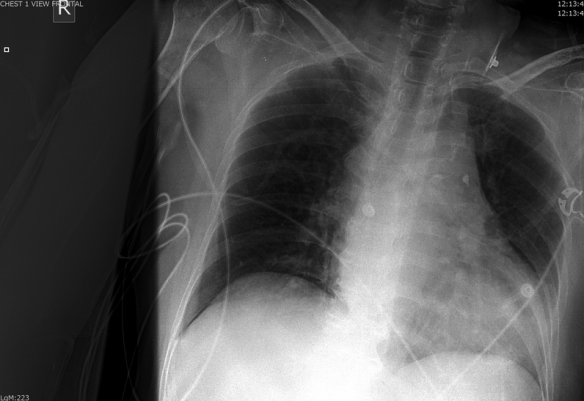

Though it was atypical for the patient to be hypotensive and tachycardic, the presence of a pericardial effusion without tamponade suggested aortic dissection to me.  My attending got on the phone to prepare to transfer the patient while I contacted the radiologist to clear the CT scanner.  Though I attempted to view the descending aorta and aortic outflow tract on a more focused echo in the brief interim through a parasternal approach, I was unable to obtain good windows.  The IVC was plump and the rest of the FAST was negative.  A quick Chest XR was done:

Screen Shot 2013-08-22 at 6.21.01 PM

…..which did not show a wide mediastinum according to radiology.  The patient was whisked away to the CT scanner and within 45 minutes of ED arrival, the diagnosis of a Stanford type A aortic dissection with pericardial effusion (but not tamponade) was confirmed.  This would not have been possible without bedside ultrasound as I think most clinicians would have been falsely reassured by the normal CXR (widened mediastinum only present in 60% of aortic dissections1).